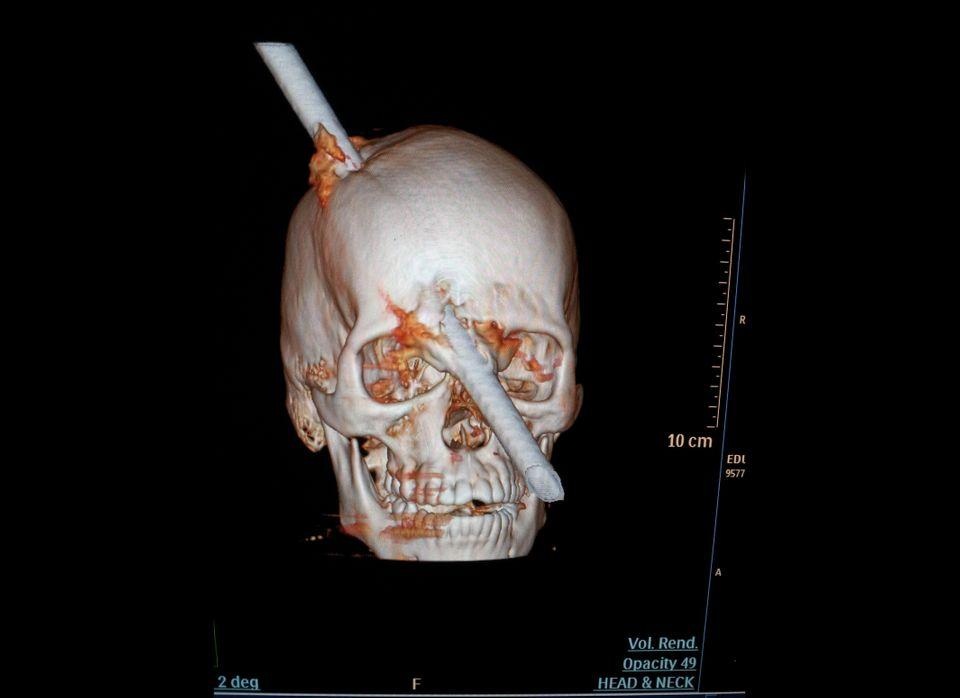

Bức ảnh chụp cắt lớp này được bệnh viện Miguel Couto công bố ngày 16/8/2012. Đây là trường hợp bệnh nhân 24 tuổi, là công nhân xây dựng và bị tai nạn thanh sắt từ trên cao rơi trúng đầu trong khi làm việc ở Rio de Janeiro (Brazil). Các bác sĩ cho biết bệnh nhân may mắn vì thanh sắt dài 15cm xuyên đúng giữa 2 chân mày qua sau đầu và các bác sĩ đã mất hơn 5 tiếng để lấy thanh sắt này ra.